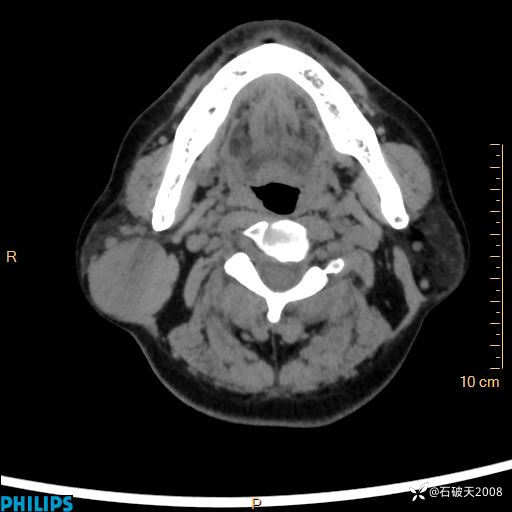

病例分享:颈部占位,一周后公布病理

男 57岁 主 诉:发现右侧颌下肿物1月余。

现病史:1月余前家属发现右侧颌下肿物。局部皮肤无红肿、热痛,无吞咽困难,无异物感,无恶心、呕吐,无头痛、头晕,无胸闷、胸痛,无发热、咳嗽、咳痰及呼吸困难。于我院行体表肿块彩超检查(2024.03.15我院)示:右侧耳下皮下软组织内低回声,未治疗。今为进一步治疗门诊以“腮腺肿瘤”为诊断收住我科,发病来患者神志清,精神可,饮食、睡眠及大小便正常,体重无明显下降。

平扫